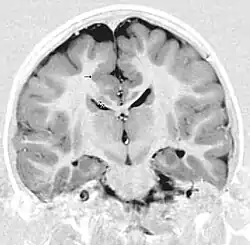

Neuroimaging

The diagnosis of polymicrogyria is typically made by magnetic resonance imaging (MRI) since computed tomography (CT) and other imaging methods generally do not have high enough resolution or adequate contrast to identify the small folds that define the condition. The cerebral cortex often appears abnormally thick as well because the multiple small gyri are fused, infolded, and superimposed in appearance.[5]

Gross neuropathologic examination reveals a pattern of complex convolutions to the cerebral cortex, with miniature gyri fused and superimposed together, often resulting in an irregular brain surface. The cortical ribbon can appear excessively thick as a result of the infolding and fusion of multiple small gyri.[5]

Microscopic examination demonstrates that the cerebral cortex is in fact abnormally thin and has abnormal lamination; typically the cortex is unlayered or has four layers, in contrast to the normal six layers. The most superficial layers between adjacent small gyri appear fused, with the pia (layer of the meninges) bridging across multiple gyri. Prenatal diagnosis for BFPP is also available for pregnancies at risk if the GPR56 mutations have been identified in an affected family member.[5]

- Radiological findings (MRI) demonstrated symmetric generalized polymicrogyria with decreasing anterior-posterior gradient, most prominent in frontoparietal cortex.[5]

- Numerous gyrus on the cortex

- Small gyri and sulci

- Thin cortex